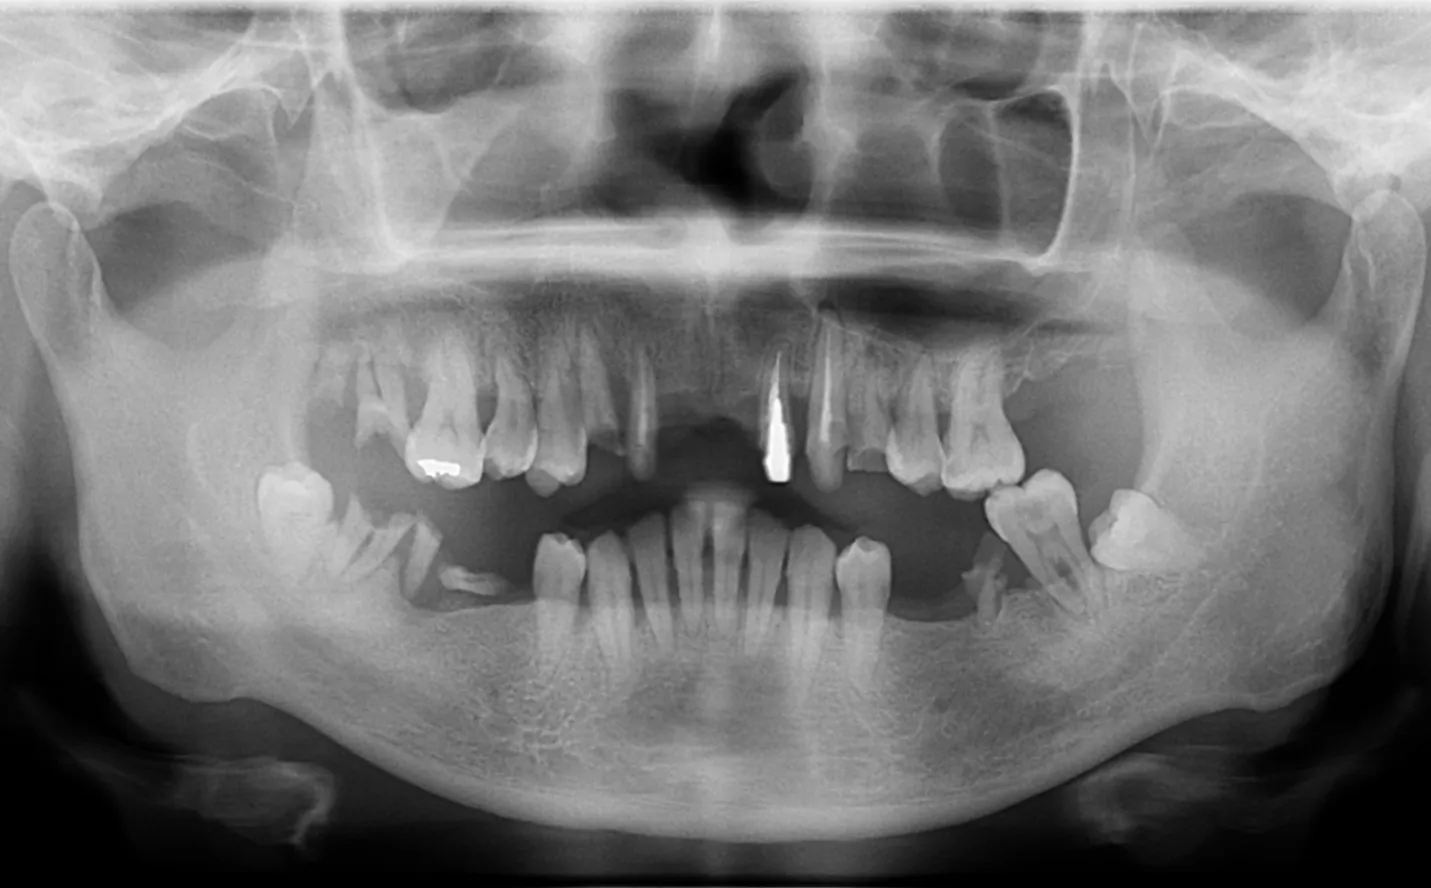

【症例2】

主訴

前歯の被せ物が外れた。綺麗に治したい。

年齢・性別

40代男性

治療内容

右上3~左上2に対して

・インプラントブリッジ

左右6に対して

・インプラント

他数本に対して

・セラミック

期間

1年4ヶ月

費用

3,583,000円